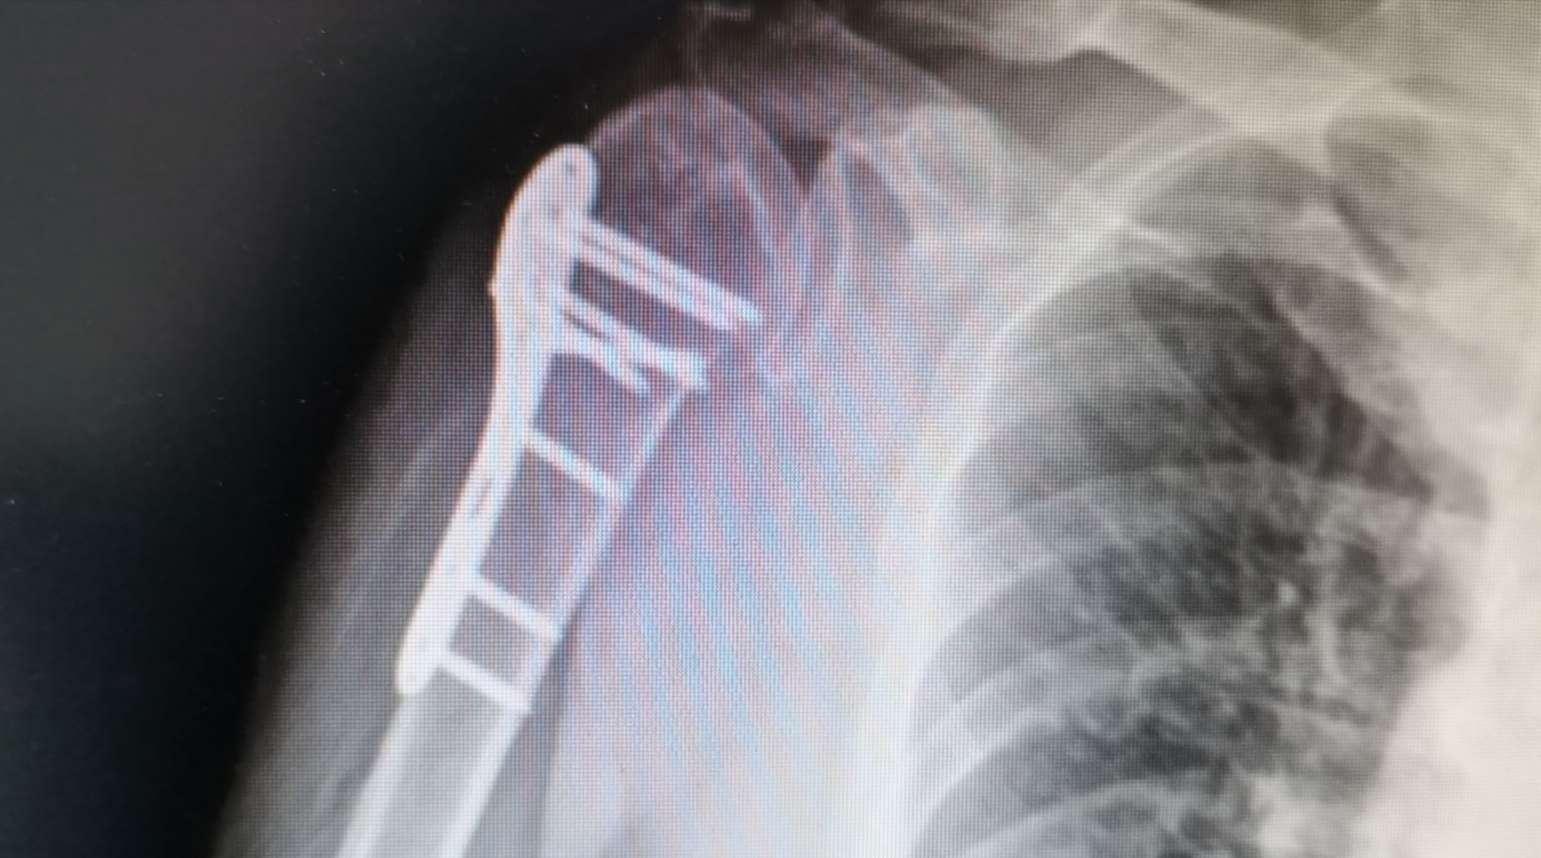

【摘要】   目的:探讨不稳定肱骨近端骨折患者钢板内固定术后发生肱骨头内翻的影响因素。  方法: 回顾性分析 2019 年 1 月至 2020 年 1 月该院收治的 60 例行钢板内固定术治疗的不稳定肱骨近端骨折患者的临床资料。随访 1 年,统计肱骨头内翻发生率,对不稳定肱骨 近端骨折患者钢板内固定术后发生肱骨头内翻的相关因素进行单因素和多因素 Logistic 回归分析。  结果: 60 例不稳定肱骨近端骨折患者钢 板内固定术后发生肱骨头内翻 11 例,发生率为 18.33%,  未发生肱骨头内翻 49 例;发生肱骨头内翻患者受伤机制、骨质疏松、肱骨距螺 钉置入、术中肱骨颈干角与未发生肱骨头内翻患者比较,  差异有统计学意义(P<0.05);  多因素 Logistic 回归分析显示,  肩关节外旋位损伤、 骨质疏松、未置入肱骨距螺钉、术中肱骨颈干角 <125°或 >145°均为影响不稳定肱骨近端骨折患者钢板内固定术后发生肱骨头内翻的独 立危险因素(OR>1,  P<0.05)。  结论: 骨质疏松、未置入肱骨距螺钉、术中肱骨颈干角 <125°或 >145°均为影响不稳定肱骨近端骨折患 者钢板内固定术后发生肱骨头内翻的独立危险因素。

【 Abstract 】  Objective: To explore influencing factors of humeral head varus after plate internal fixation in patients with unstable proximal humerus fractures. Methods: The clinical data of 60 patients with unstable proximal humerus fractures treated by plate internal fixation in our hospital from January 2019 to January 2020 were retrospectively analyzed and followed up for 1 year. The incidence of humeral head varus was analyzed. Univariate and multivariate Logistic regression analysis were performed to analyze the related factors of humeral head varus after plate internal fixation in the patients with unstable proximal humerus fractures. Results: In the 60 patients with unstable proximal humerus fractures, 11 cases of humeral head varus occurred after the plate internal fixation with an incidence rate of 18.3%, and 49 cases did not have humeral head varus. There were significant differences in injury mechanism, osteoporosis, humeral calcar screw placement, and intraoperative humeral neck-shaft angle between the patients with humeral head varus and those without humeral head varus (P<0.05). Multivariate Logistic regression analysis showed that external rotation injury of the shoulder joint, osteoporosis, no humeral calcar screw placement, and intraoperative humeral neck shaft angle <125° or >145° were all the independent risk factors for humeral head varus in the patients with unstable proximal humerus fractures after plate internal fixation (OR>1, P<0.05). Conclusions: Osteoporosis, no humeral calcar screw placement, and the intraoperative humeral neck shaft angle <125° or >145° are all the risk factors for humeral head varus in the patients with unstable proximal humerus fractures after plate internal fixation.

1.2   方法   肱骨头内翻判定标准:骨折愈合后仍 存在成角、旋转或重叠畸形,没有复位至功能位 置,  肱骨近端正位 X 线片显示肱骨颈干角(肱骨长 轴与肱骨头中轴夹角)<120°则判定为发生肱骨头 内翻。

2.1   不稳定肱骨近端骨折患者内固定术后肱骨头 内翻发生情况   术后 1 年,  60 例不稳定肱骨近端 骨折患者钢板内固定发生肱骨头内翻 11 例,发生 率为 18.33%,  未发生肱骨头内翻 49 例。

本研究结果显示,  60 例不稳定肱骨近端骨 折患者锁定钢板内固定术后发生肱骨头内翻 11 例,  发生率为 18.33%。  多因素 Logistic 回归分析 结果显示,肩关节外旋位损伤、骨质疏松、未置 入肱骨距螺钉、术中肱骨颈干角 <125°或 >145° 均为影响不稳定肱骨近端骨折患者钢板内固定术 后发生肱骨头内翻的独立危险因素。分析原因如 下:   (1)肩关节外旋位损伤。依据患者受伤时不 同体位可将患者分为肩关节外旋位损伤、肩关节 内旋位损伤,创伤发生时肩关节外旋可出现内收 型骨折,肩关节内旋可出现外展型骨折,其中肩  关节外旋位损伤所致的内收型骨折肱骨近端内侧 骨皮质损伤一般较为严重,多为粉碎性骨折,复 位难度相对较大,加之肩袖内翻应力增加,易出  现固定不稳情况,增加术后肱骨头内翻发生风 险 [6-7]。(2)骨质疏松。存在骨质疏松的患者骨强 度降低、骨脆性增加,相同负荷下此类患者更易发 生骨折,且骨质疏松患者骨密度较低,易减弱钢板 内固定抗压程度及把持力,  增高钢板内固定失败率, 引发肱骨头内翻 [8-9]。( 3)未置入肱骨距螺钉。肱 骨距主要指肱骨头与干交界处内下侧皮质区域,此 区域骨皮质厚度及骨密度最佳,在该区域置入螺钉 可有效减小剪切应力,增加钢板内固定稳定性。而 未置入肱骨距螺钉的患者钢板内固定稳定性欠佳, 术后发生肱骨头下沉概率较大,增高肱骨头内翻发 生率 [10-11]。( 4)术中肱骨颈干角 <125°或 >145°。

正常肱骨颈干角在 125° ~145°之间,术中肱骨颈 干角 <125°或 >145°的患者易发生复位丢失,增 大剪切应力,限制术后肩关节活动,易导致肱骨 头塌陷,出现畸形愈合,增加肱骨头内翻发生风 险 [12-13] 。基于上述原因,  临床应嘱咐患者合理补充 钙剂和维生素 D,改善骨质疏松状况;手术过程中 置入肱骨距螺钉、尽可能恢复肱骨颈干角,以降低 不稳定肱骨近端骨折患者钢板内固定术后肱骨头内 翻发生率 [14]。

综上所述,骨质疏松、未置入肱骨距螺钉、术中肱骨颈干角 <125°或 >145°均为不稳定肱骨近端骨折患者钢板内固定术后发生肱骨头内翻的影响 因素。